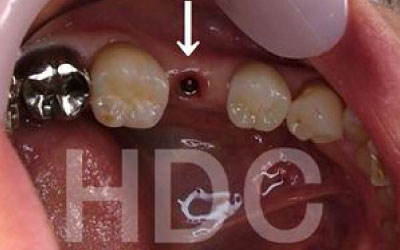

今回のご質問ですが、抜けた部分の骨が薄いなどの理由で「インプラントはできない」と言われた可能性があります。

前歯はもともと骨が薄く、歯が抜けると時間の経過とともにさらに骨が痩せてきてしまうので、インプラント治療の難易度が高い場所です。

ただ結論からお話すると、インプラント治療は可能です。

なぜなら、もし仮に骨が薄くても、骨の治療によって厚みが増せば、安全にインプラント治療が行えるからです。

なお、前歯のインプラント治療をご希望の方には、注意していただきたい点が4つほどあります。

1)インプラント治療を行う前に、骨の治療が必要かもしれません。

2)骨の治療から始めると、その分、治療期間が長くなります。

3)骨の治療は、通常のインプラント治療よりも難易度が高いため、経験の豊富な先生やインプラント認定医のいる歯科医院で治療を受けることをお勧めします。

4)骨の状況をしっかり把握するためにも、CT撮影が必須となります。